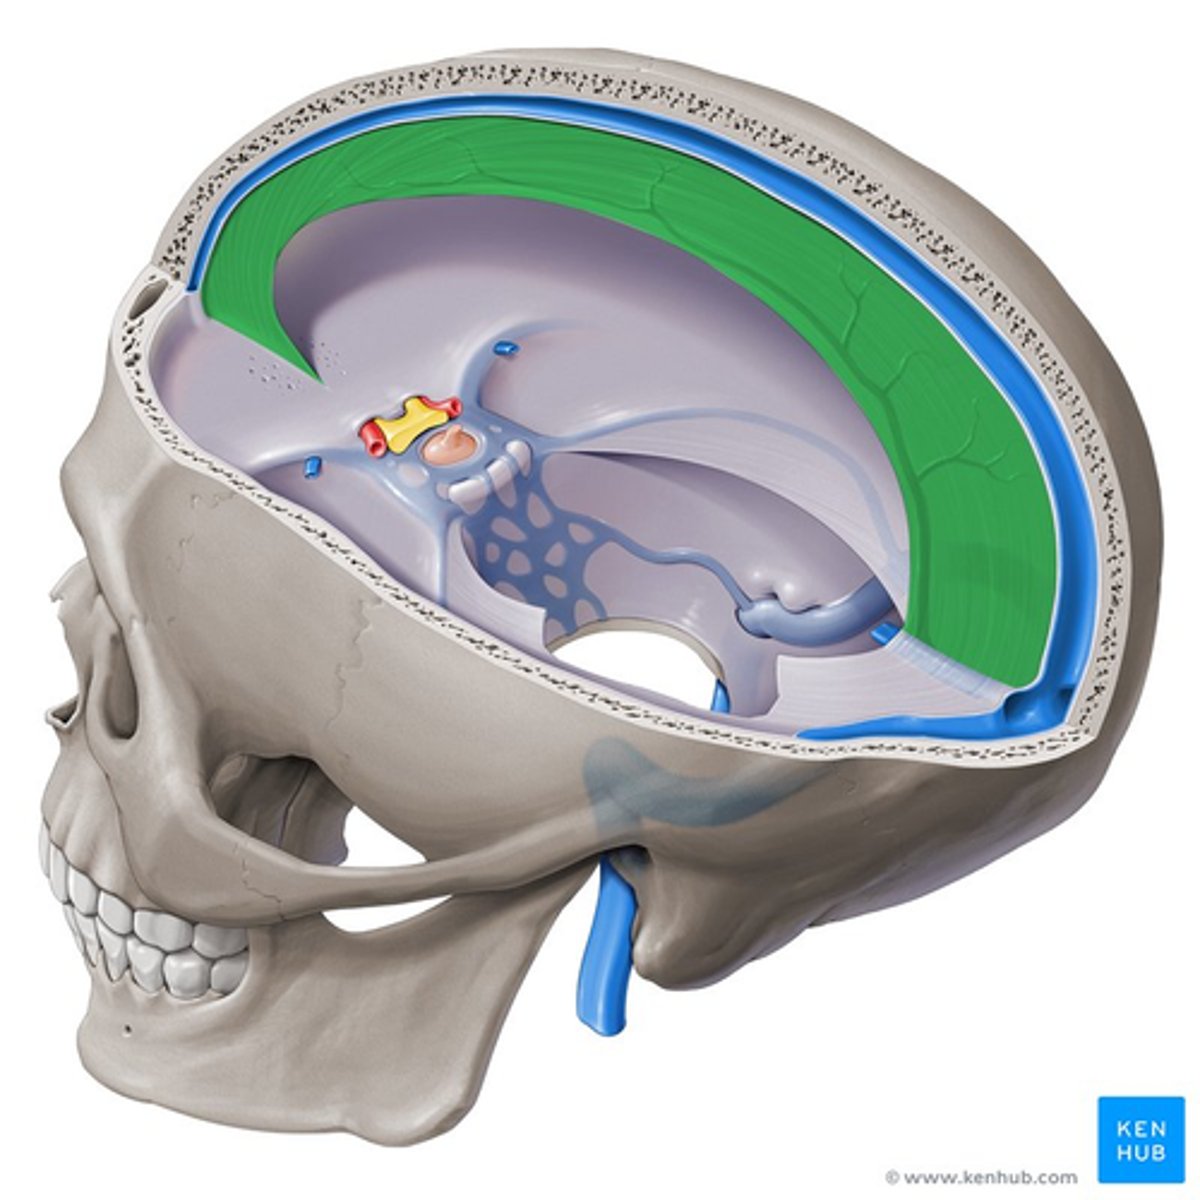

falx cerebri

sickle shaped, separates two hemispheres

tentorium cerebelli

shelf-like, separates cerebellum from cerebrum

tentorium cerebelli

falx cerebri